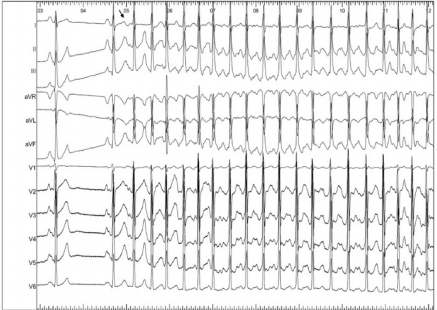

The real turning point in the long history of the AF was in 1998 when Haissaguerre first demonstrated the role of pulmonary veins (PV), offering a still valid target for a pathophysiological approach to AF ablation, through the electrical isolation of them [3]. The anatomical, histological and electrical discontinuity in the area between PVs and the left atrium has provided basis for several studies aimed at identifying the pathophysiological mechanisms responsible for the AF initiation and maintenance. The atrial myocardium consists of one to three muscular layers superimposed according to the regions and extends for 1-3cm to cover the initial PVs tracts, forming muscular sleeves that surround veno-atrial connecting zone [4]. These sleeves play a role in the regulation of pulmonary venous flow. Both for their histological properties and for their cellular peculiarities, the sleeve’s myocytes represent an important arrhythmogenic substrate. From a histological point of view, this zone of veno-atrial connection represents an architectural discontinuity point; this discontinuity promotes micro-reentry mechanisms and constitutes a substrate that can trigger rapid focal ectopic activity. This early ectopic activity, originating from PVs hosts, manifests itself with the so-called electrocardiographic “P on T” phenomenon, with very early extra systolic beats, as an expression of the short refractory nature of the pulmonary vein muscles (Figure 1). Focal extrapulmonary foci, which can trigger atrial fibrillation, such as the Marshall ligament, the crista terminalis, the coronary sinus ostium, the posterior wall of the left atrium or more commonly the superior vena cava are described in literature, as well [5] (Figure 1).

Figure 1: “P on T” phenomenon on surface ECG. After the first two sinus beats, a very early atrial ectopic premature beat (see the arrow) triggers atrial fibrillation. The ectopic beat is so premature that the P wave is inscribed inside the T wave of the previous beat (P on T phenomenon). This behaviour is typical for pulmonary veins ectopic beats triggering atrial fibrillation.